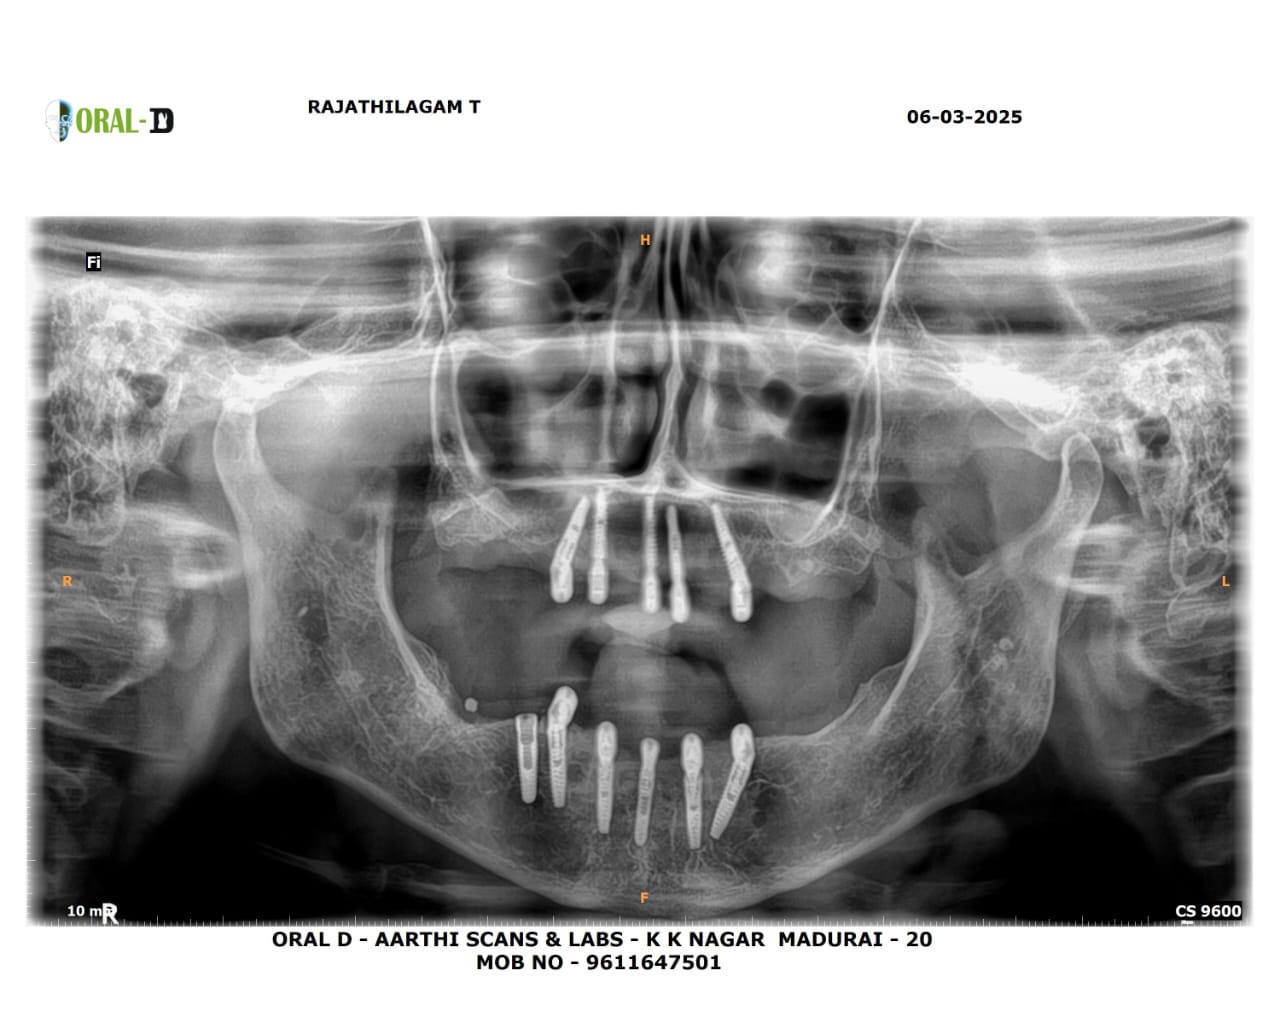

Images Of Dental Treatment Servcies Done At Our Hospital